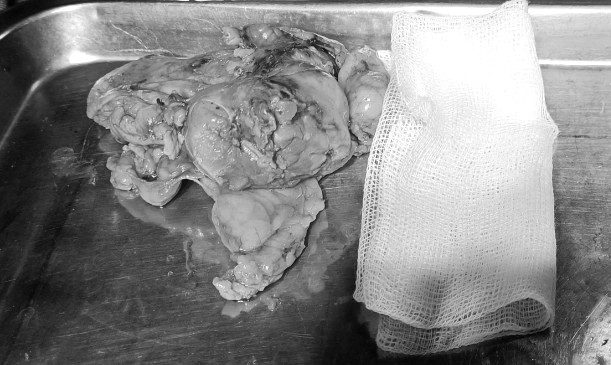

![]() |

| Phần thận chứa khối u và tổ chức mỡ xung quanh được nội soi lấy ra thành công - Ảnh BVCC |

Kết quả giải phẫu bệnh sau mổ với diện cắt và tổ chức mỡ quanh u không có tế bào ung thư, chẩn đoán xác định là ung thư biểu mô tế bào sáng. Với vết mổ nhỏ ít xâm lấn, sức khoẻ bệnh nhân tiến triển tích cực, xuất viện sau 1 tuần điều trị.